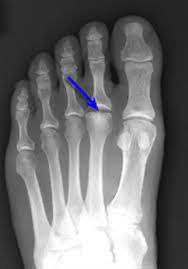

Freiberg Disease

• Avascular necrosis of metatarsal head, most commonly 2nd toe

• Commonly in females

• X-ray of a foot with a blue arrowDescription automatically generated